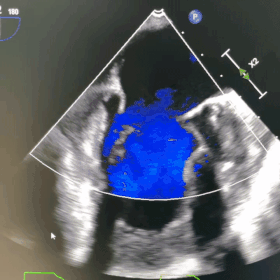

术前超声

患者2月前出现活动后乏力气喘伴有咳嗽咳痰,与当地医院治疗效果不佳,于武汉协和门诊行心脏超声检查提示:左室壁运动弥漫性稍减弱;二尖瓣重度关闭不全;主动脉瓣退行性病变并中度关闭不全;三尖瓣轻度关闭不全;左心增大;右房饱满;升主动脉明显增宽;肺动脉增宽;轻度肺高压;左室收缩功能测值减低,舒张功能减低(Ⅱ级)。患者为进一步诊治,遂以“二尖瓣关闭不全“收入院。